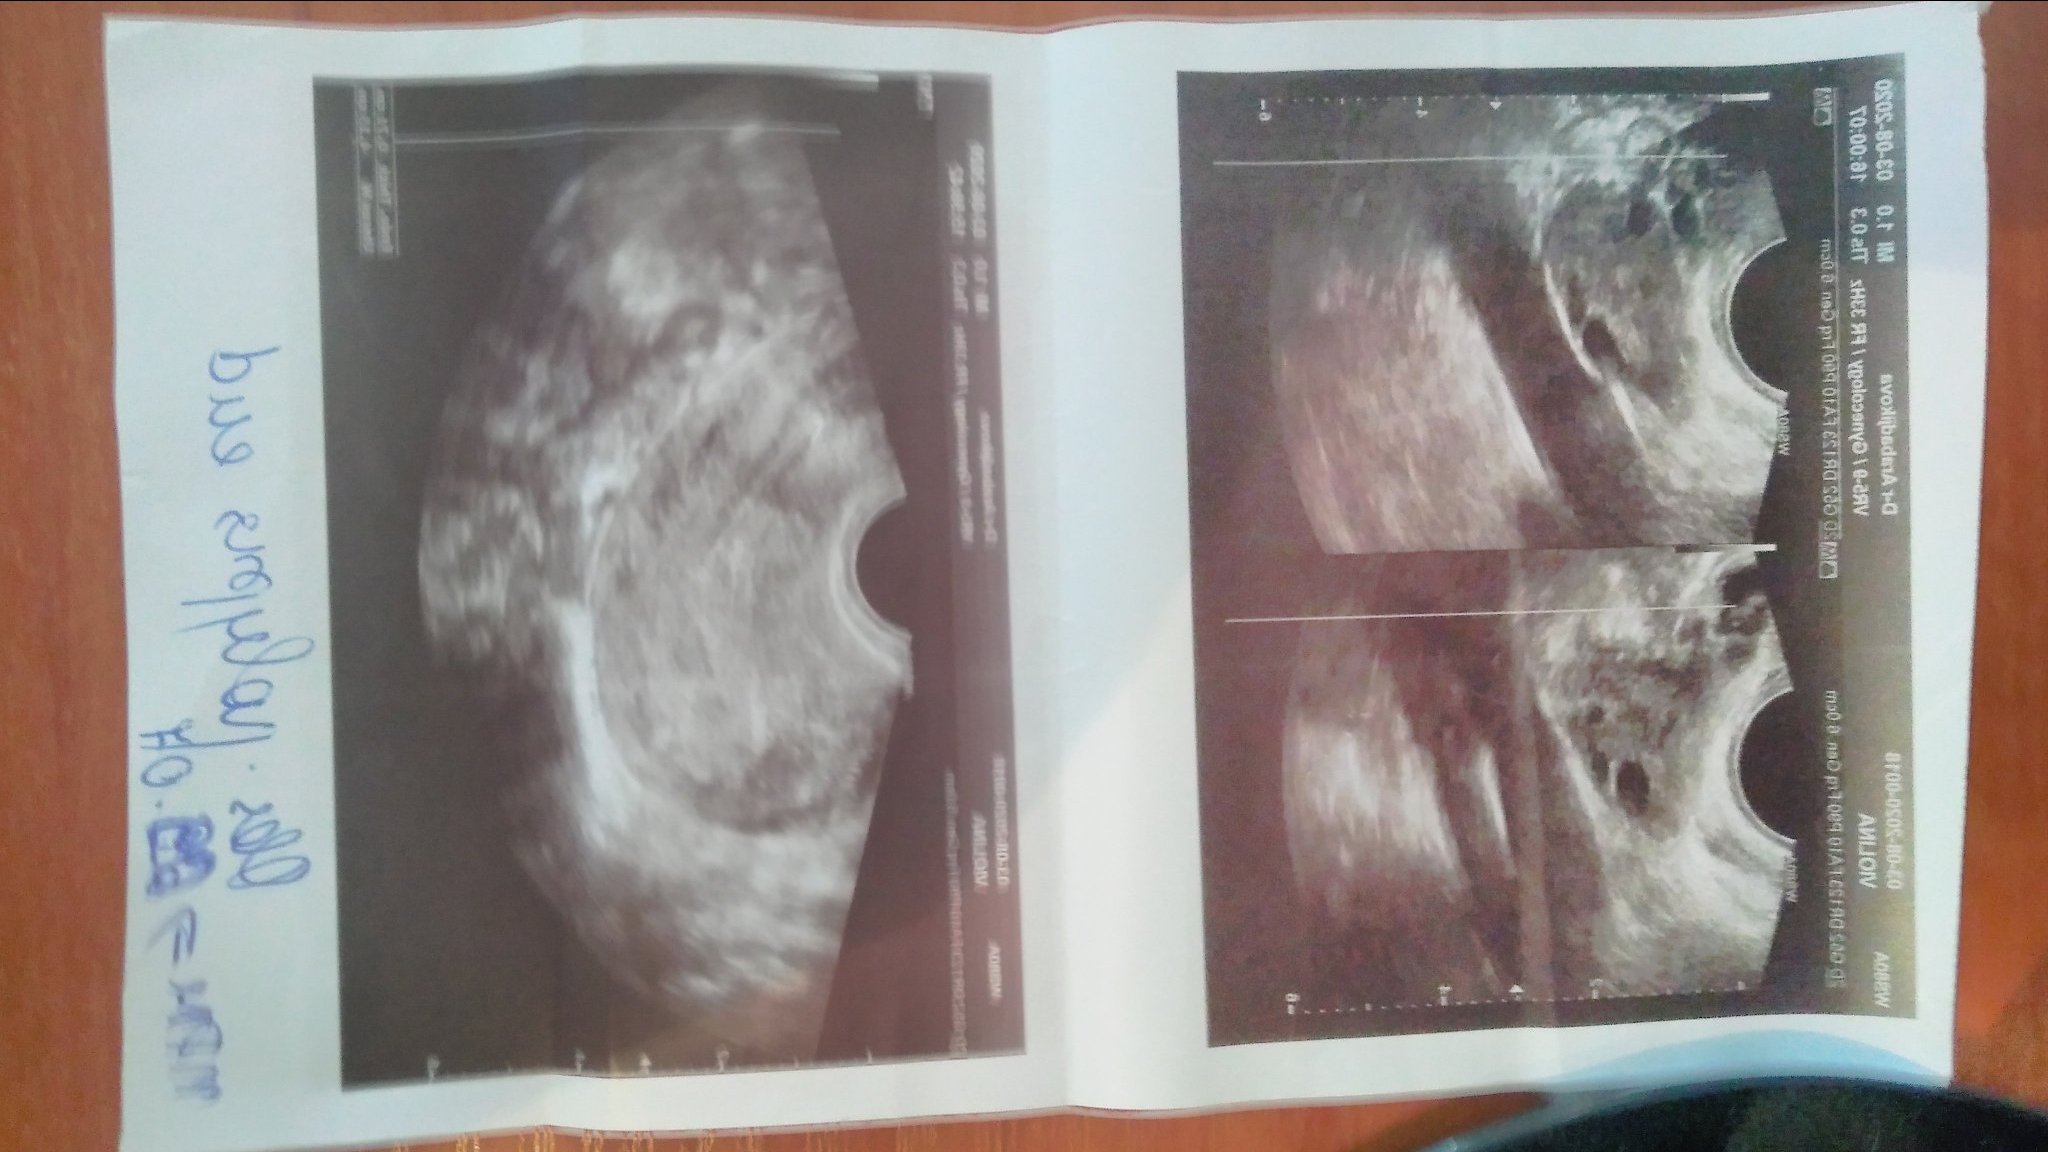

Някой може ли да разчете тази снимка и на мен ми казаха полип на лигавицата,но в паниката от това което ми казват забравих да питам колко е голям.Благодаря